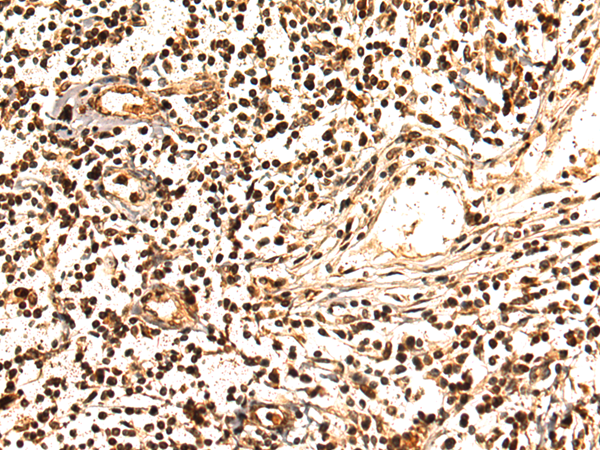

IHC positive control: |

Human breast cancer |

IHC Recommend dilution: |

50-100 |